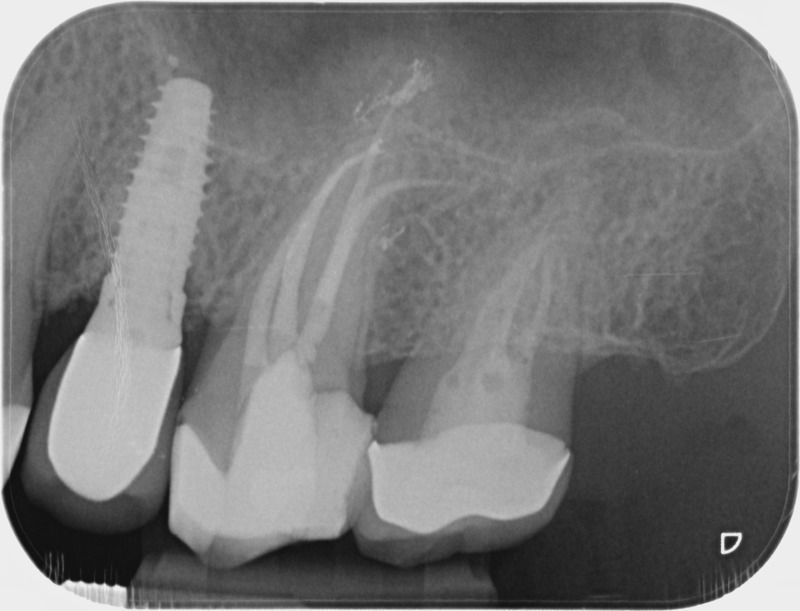

• Traitement endodontique : Sous anesthésie locale et à travers la protection d’un champ opératoire nous accédons à la pulpe de la dent à soigner, puis aux canaux de ses racines que nous devons désinfecter. Ce soin nécessite l’élimination complète de la source de contamination (souvent la carie) parfois sous une ancienne reconstitution ou une couronne qu’il faut alors retirer. Une fois le nettoyage et la mise en forme des canaux réalisés, nous les obturons de façon hermétique avec un ciment et un matériau thermoplastique appelé Gutta Percha. Ceci afin d’empêcher une nouvelle prolifération bactérienne et d’assurer le maintien de la dent dans ses structures de soutien (ligament parodontal et os alvéolaire). L’ouverture effectuée au centre de la dent sera d’abord refermée avec un pansement provisoire avant d’envisager ensemble la reconstitution d’usage : un composite, un inlay-onlay ou une couronne.

Après